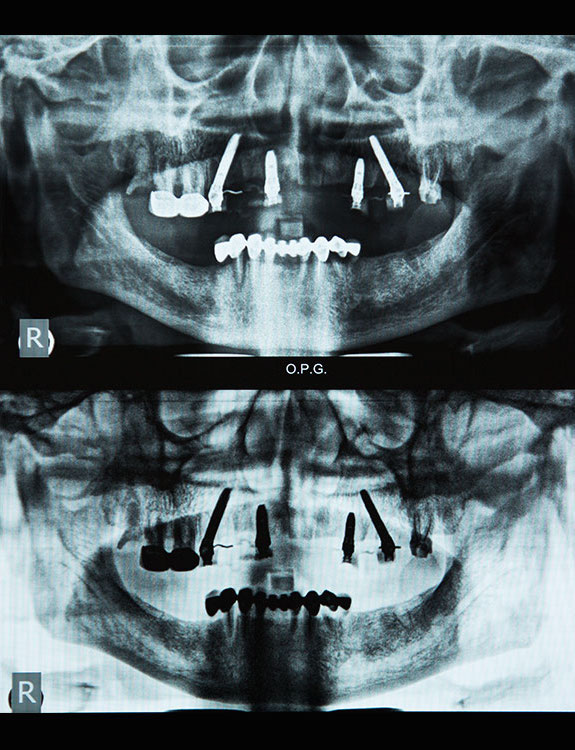

Dental implants are artificial tooth roots made of medical-grade titanium that are surgically placed into the jawbone. Once the implant integrates with the bone, a crown is fixed on top, giving you a strong, natural-looking replacement tooth.

When compared to bridges or dentures, dental implants offer unmatched comfort and longevity.

Dental implant treatment requires specialized training and experience. Choosing a qualified Implantologist in Punjabi Bagh like Dr Sumit Dutta or Dr Harsha Dutta ensures: